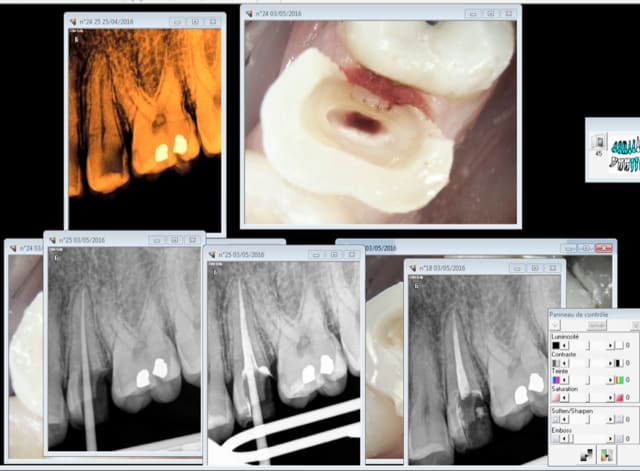

Rentrons dans le vif du sujet Ces 2 cas justifient ils de recourir à un inlay core ?

J ai vu des cas comme ceux là gères en endocouronne à recouvrement très partiel hormis la partie proximité, sans objection de ma part. (no post je precise)

Je n en verrai pas plus pour une option thérapeutique inlay core couronne.

Cas concret la rétro coronaire de cette 35 nous montre une grosse lésion carieuse. Je fais donc une rétro alvéolaire pour voir si il n'y a rien à l'apex et qui me servira de radio pré op dans le cas probable d'une endo. je ne vais pas irradier le patient inutilement pour avoir la totalité de la 46 et éviter un indu potentiel . Non ? -)